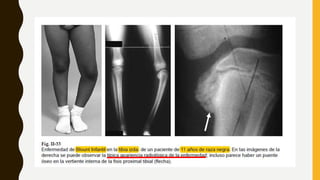

BLOUNT INFANTIL O DE INICO PRECOZ:

BLOUNT ADOLESCENTE: >10 años

• Unilateral (80%)

• Discrepancia de longitud.

• Dolor e inestabilidad en rodilla.

• Alteración del fémur distal

• Varo

• Deformidad de la tibia

• Obesidad, raza negra.

IMAGENOLOGÍA

• Tele-radiografia EEII

• Evaluar bilateralidad y

simetría

• Grado de angulación

Se deben solicitar radiografías de

ambas rodillas en proyección

anteroposterior y lateral, así como

una telerradiografía.

 HALLAZGO PATOGNOMÓNICO

* Distorsión epifisio-fisio-

metafisiaria